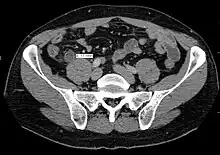

Computed tomography

Where it is readily available, computed tomography (CT) has become frequently used, especially in people whose diagnosis is not obvious on history and physical examination. Concerns about radiation tend to limit use of CT in pregnant women and children, especially with the increasingly widespread usage of MRI.[49][50]

The accurate diagnosis of appendicitis is multi-tiered, with the size of the appendix having the strongest positive predictive value, while indirect features can either increase or decrease sensitivity and specificity. A size of over 6 mm is both 95% sensitive and specific for appendicitis.[51]

However, because the appendix can be filled with fecal material, causing intraluminal distention, this criterion has shown limited utility in more recent meta-analyses.[52] This is as opposed to ultrasound, in which the wall of the appendix can be more easily distinguished from intraluminal feces. In such scenarios, ancillary features such as increased wall enhancement as compared to adjacent bowel and inflammation of the surrounding fat, or fat stranding, can be supportive of the diagnosis. However, their absence does not preclude it. In severe cases with perforation, an adjacent phlegmon or abscess can be seen. Dense fluid layering in the pelvis can also result, related to either pus or enteric spillage. When patients are thin or younger, the relative absence of fat can make the appendix and surrounding fat stranding difficult to see.[52]